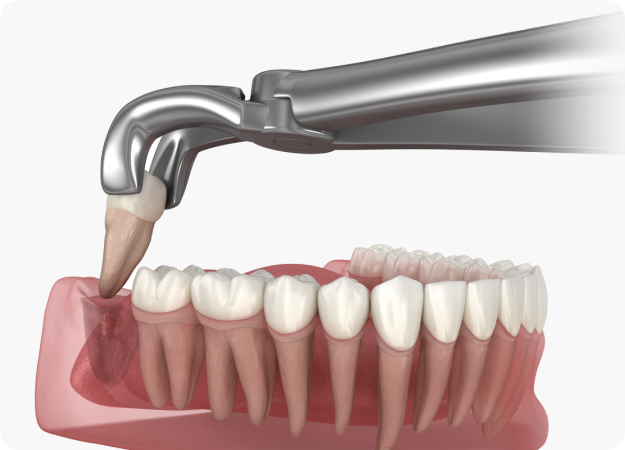

예쁘게 나온 사랑니를 뽑는 것도 무서운데

매복된 사랑니를 뽑는다는 공포는

말로 표현할 수 없을 것입니다.

서울큰치과에서는 숙련된 의료진의 노하우를 적용한 의식하진정요법으로 정확하고 안전하게 사랑니를 발치할 수 있습니다.

사랑니를

발치하지 않으면.

음식물 찌꺼기가 잘 껴서 충치나 잇몸질환, 구취의 원인이 되며, 다른 치아의 염증으로 전이될 수도 있습니다. 따라서 정확한 진단 후 깔끔하게 발치하는 것이 좋습니다.